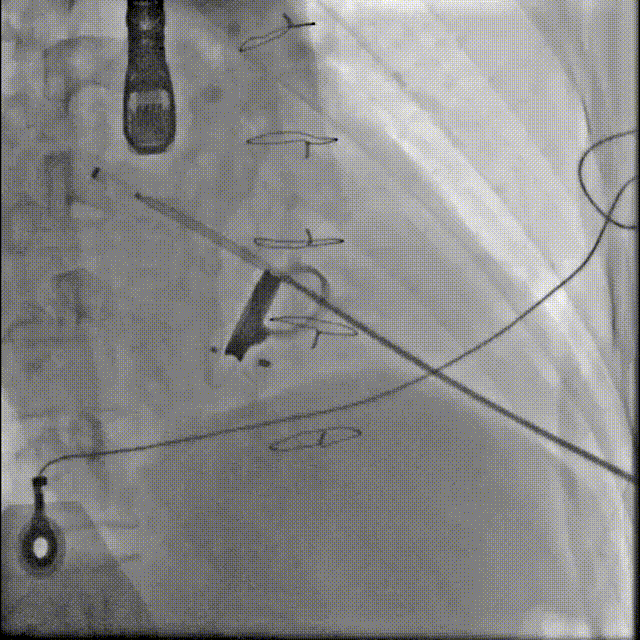

手术操作

1.患者平卧位,食道超声检查瓣周漏位置及大小,并引导穿刺心尖,选择7F鞘管通过10点位置瓣周漏口,将单弯导管送入左心室,置换超硬导丝至左心室,选择12-14mmPDAO封堵10点位漏口。

3.选择7F鞘管通过1-2点位置瓣周漏,彩超显示鞘管对瓣周漏口的影响较小,结合漏口大小,选择14-16mmPDAO封堵此处漏口。

术后封堵器形态位置